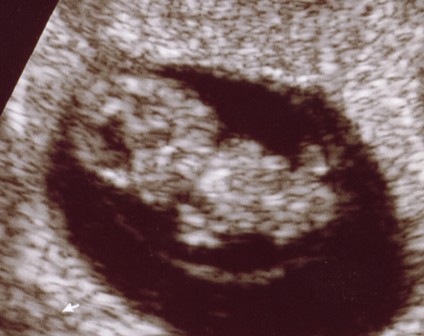

mérés szerint CRL 10mm és 7+2

Baby Leo :lol: :lol: :lol: :lol:

Tökéletes bébi (ezt tudtam eddig is :wink: )

MrsLeo: Nagyon jó! Már egészen emberformája van! :D Azért te sem bírtad ki a 12. hétig :wink: Hátha én is ilyen klassz képet kapok szerdán :roll: :roll: :roll: :lol: